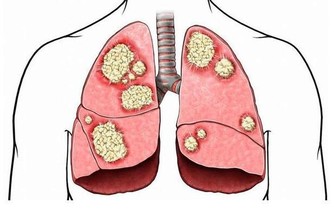

防癌:一顆洋蔥隨便吃

洋蔥中所含有山奈酚和檞皮黃酮等成分, 能夠阻止癌細胞的血管生成, 可防治乳癌、胃癌及其他癌症的發生。

山東省的一個研究也發現:當洋蔥吃得越多, 得胃癌的機率越低。